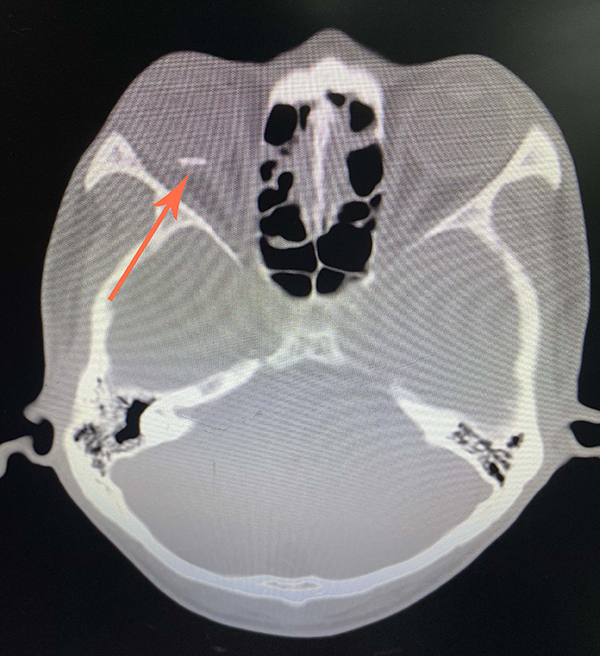

楊先生意識到,有東西飛進了他的眼睛。他連夜到當地醫院就診。醫生給他做了裂隙燈和眼眶CT等檢查,發現他的眼球內有一個異物,診斷其為右眼球穿通傷并球內異物、右眼外傷性白內障。

做入院檢查時,醫生發現楊先生只能看見眼前的手在晃動,至于幾根手指在動,他看不清。此外,楊先生的角膜有一道長約7毫米的全層破裂口,晶狀體全變白了,眼底視網膜的情況完全看不見。

我院眼科按急診流程第一時間為楊先生做了角膜穿通傷清創縫合及白內障超聲乳化摘除聯合25G微創玻璃體切割手術,以最小的損傷順利地將患者眼球內的異物取出。

醫務人員發現取出來的異物表面有一層黑黑的炭灰,把炭灰擦去后大家發現:異物的表面居然有一排字母。該異物到底是什么爆炸產生的碎片?經仔細辨認,醫生們猜測,可能是丟棄在火堆里的瓶子遇到高溫后爆炸產生的。

據醫生介紹,因異物飛行的速度很快,打穿了楊先生的角膜和晶狀體,針對患者的病情,醫生對其實施了角膜縫合、白內障摘除等手術。屆時,還需實施角膜縫線拆除和二期人工晶狀體植入手術。雖然患者的視網膜沒有明顯損傷,但角膜傷口引起的散光明顯,對日后的視力有較大影響,若想重新看清東西,可能要做角膜移植手術。